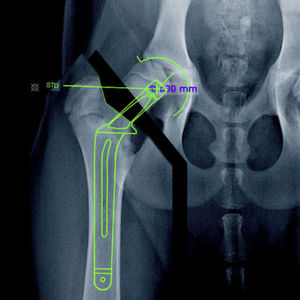

módulo de software de planificación preoperatoria

... regularmente, un flujo de software diseñado por médicos para médicos y un flujo operativo intuitivo real hacen de mediCAD® Veterinary la herramienta de planificación del futuro para la cirugía veterinaria. Su ventaja: El ...